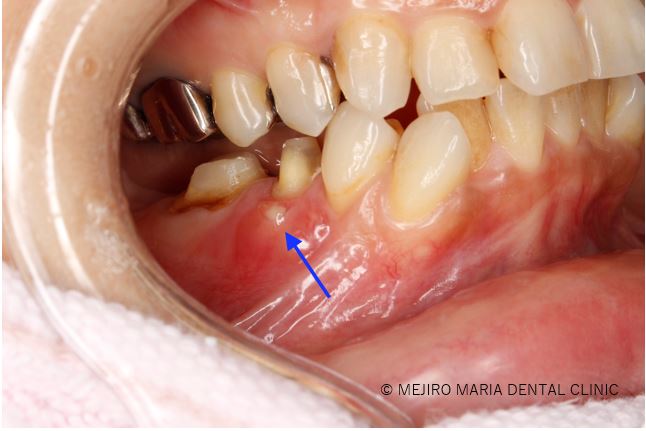

【症例】無症状で進行する虫歯・原因不明の歯肉の腫れを、コンセプトを守った初回根管治療(精密根管治療)で治癒